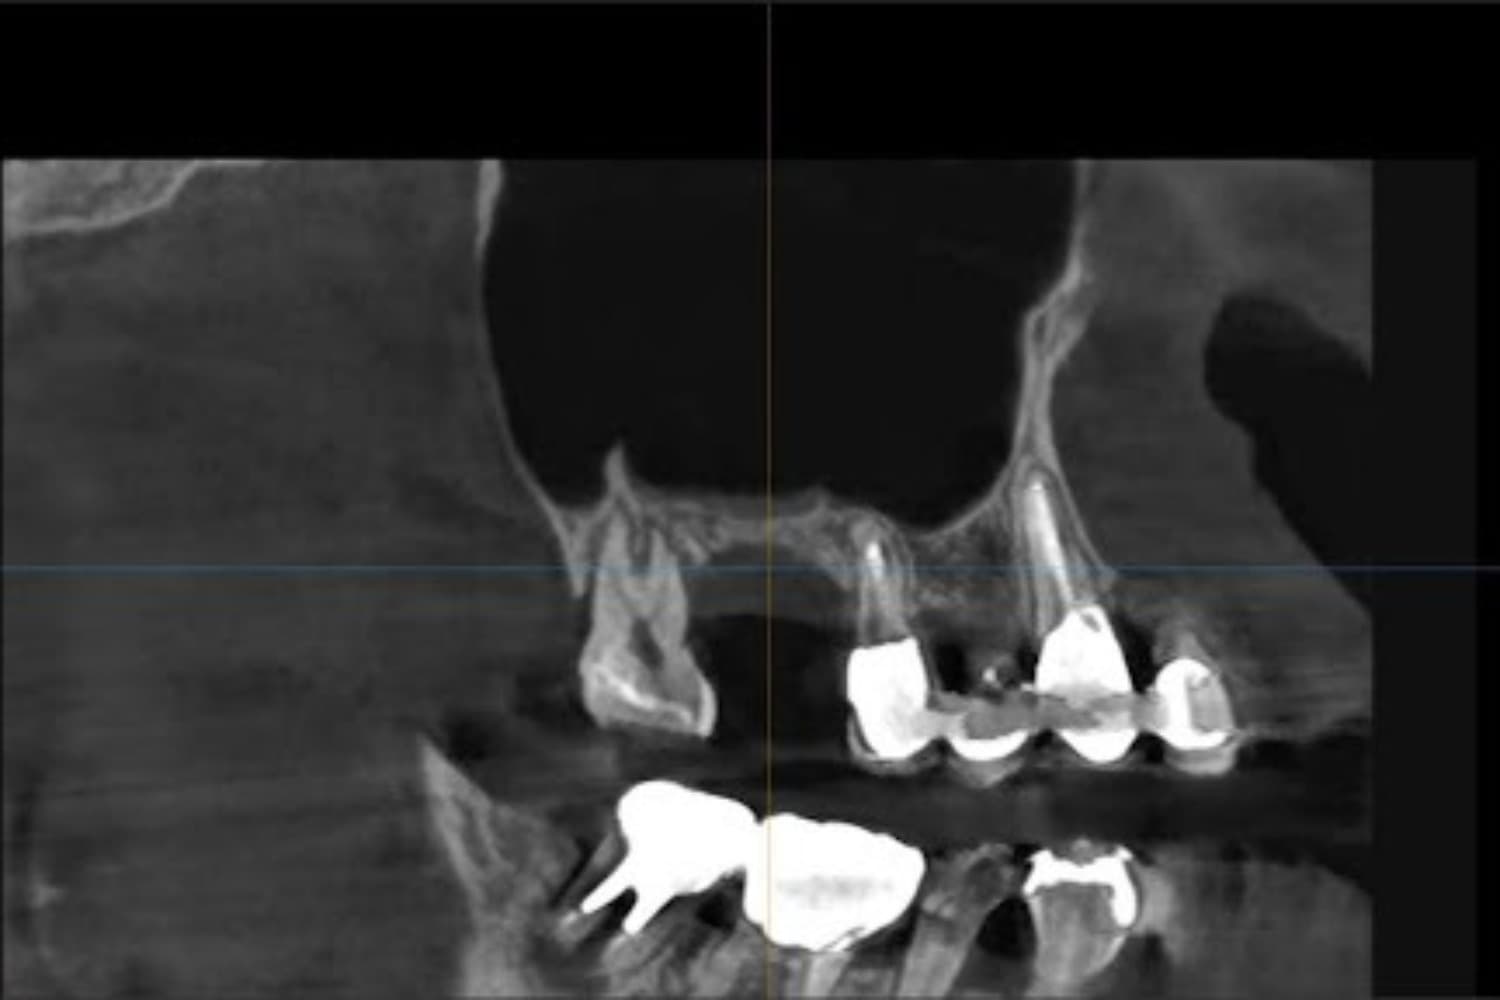

右上の歯のインプラント治療(50代女性)

Before

After

グラフトレスサイナスリフトをともなうインプラント治療

50代

女性

主訴

右上の歯が歯周病によって自然に抜け落ちてしまった

2ヵ月半

6回

363,000円(税込) 費用の内訳: 【インプラント基本料】330000円(税込み) 基本料金に以下を含む ・フィックスチャー及び手術費用 ・投薬費用、 ・レントゲン費用 ・インプラント上部費用(アバットメントおよびジルコニアクラウンの費用用) 【オプション費用】 ・グラフトレスサイナスリフト費用 33000円(税込み)

・手術後に痛み・腫れ・出血・合併症等を引き起こす恐れがあります。 ・噛む感覚がご自身の歯と異なることがあります。 ・見た目がご自身の歯と異なる場合があります。 ・手術後もメインテナンスを続けないと、インプラントが抜け落ちてしまう恐れがあります。